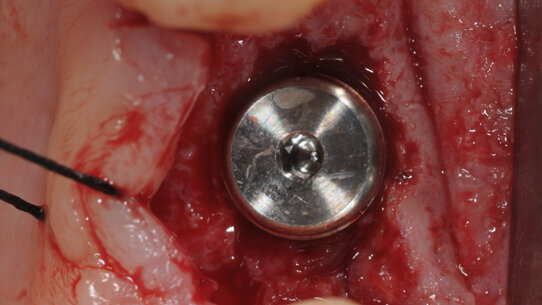

A 3 mesi dall’estrazione è stata eseguita la chirurgia di rientro e sono stati posizionati gli impianti (Intralock®, Boca-Raton, Florida, USA) sia nel gruppo test sia nel gruppo controllo. Per raccogliere i campioni nei siti innestati sono state usate frese chirurgiche trephine. Dopo il prelievo dei campioni di tessuto osseo innestato, i siti sono stati preparati secondo le raccomandazioni del produttore (Intralock®, Boca-Raton, Florida, USA). I pazienti hanno ripetuto la terapia antibiotica e antinfiammatoria del primo intervento chirurgico. I campioni prelevati sono stati codificati e inviati per l’analisi istologica al Dipartimento di Scienze mediche orali e Biotecnologie, Università degli Studi di Chieti e Pescara.

Dopo 4 mesi, gli impianti sono stati scoperti, è stata verificata manualmente la loro stabilità e sono state rilevate le impronte in polivinisilossano (Flexitime, Heraeus/Kulzer, Hanu, Germany) con portaimpronte individuali. Le protesi definitive sono state cementate e i pazienti sono stati inseriti in un programma di richiami di igiene orale ogni 3 mesi.